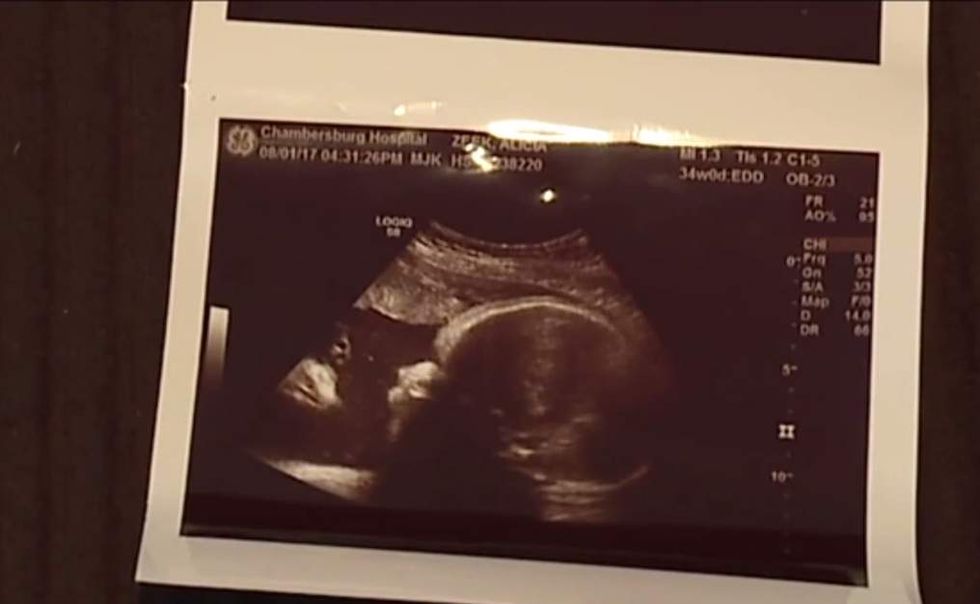

A Pennsylvania couple said they saw Jesus in their baby's sonogram. The birth of their healthy baby seems to have increased their faith. (Image source: WPMT-TV video screenshot)

The Chambersburg, Pennsylvania, couple told WPMT that while they're not very religious, they nevertheless saw a man dressed in a robe with a crown of thorns looking right at their baby in the sonogram.

Zeek's first reaction after seeing the image at their ultrasound appointment?

"I blinked a lot, to kinda make sure I was really seeing it," she told WPMT.

But when the ultrasound technician told the couple Briella looked happy and healthy, Smith told the station he and Zeek looked at the sonogram — and then he told her, "Look babe, we have nothing to worry about."

Smith said to WPMT that the image is a heavenly sign: "The angel or God or Jesus, however you want to propose it, I look at it as my blessing."